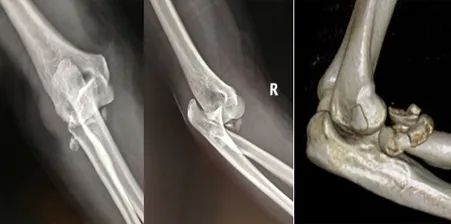

48岁的李某是梧州本地人,2020年07月17日因跌倒至肘部骨折脱位,在市内某医院拍片后明确为右肘关节脱位并桡骨头粉碎性骨折。为求中西医结合治疗来我院就诊。入院后值班医生第一时间为其行肘关节脱位闭合手法复位石膏托外固定,使患者病情转急为缓。完善检查发现患者桡骨头骨折粉碎非常严重,已经到了无法复位内固定的程度,如果勉强复位,术后一定会出现肘关节退变,活动受限的后遗症。

针对该类型骨折,以往常规采取桡骨头切除治疗,但术后常出现因桡骨短缩而导致的肘关节不稳以及下尺桡关节受累情况,后期多疼痛并活动受限。近年来我院上肢骨关节科已成功开展数例人工桡骨头置换手术。故而想到了为患者进行人工桡骨头置换治疗。 ![]() 但是,祸不单行,完善健侧的相关影像资料经测量后发现患者骨骼偏小。常规厂家提供的最小型号桡骨头假体直径为18mm,而患者健侧的桡骨头直径测量不足18mm,且按照该项技术要求,所采用假体直径要比健侧测量值小2mm左右,即直径为16mm假体,术后才能获得满意的活动功能。 针对该困局,患者曾想到放弃对良好功能的追求,行复位内固定的姑息手术。但是我院上肢骨关节科团队仍然为患者深入专研,寻求更好的治疗方案。最后有着多例上肢关节假体置换经验的何晖教授想到了定制一套符合李某自己身体情况的个体化假体进行手术治疗。听到这样的方案,患者及其家属多日的愁眉终于得以舒展。 ![]()